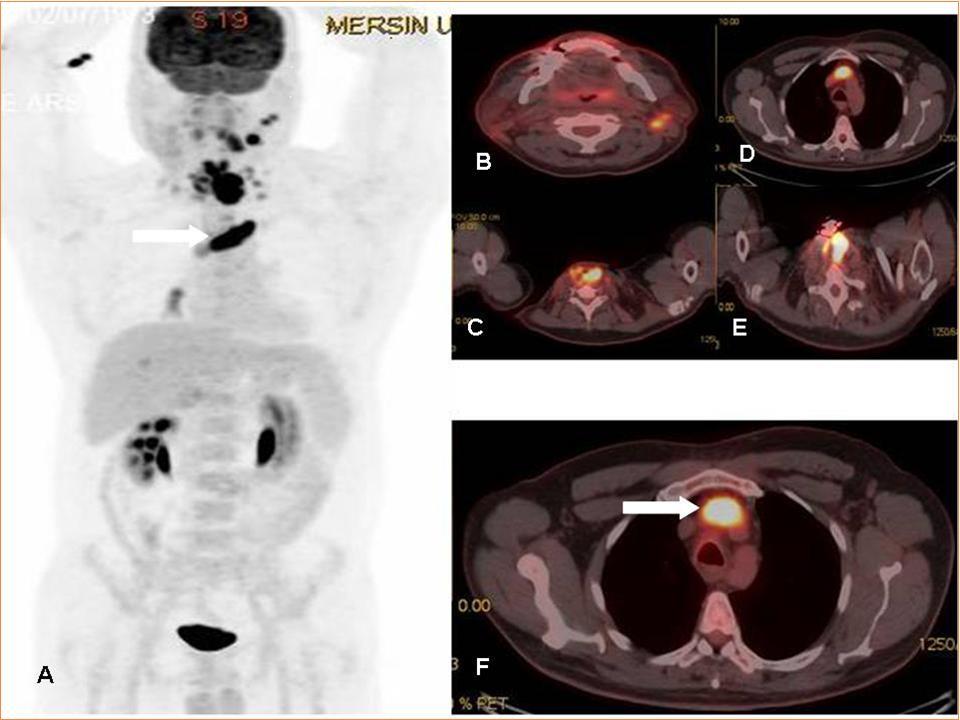

The incidence of thrombus is high in patients with underlying malignancy. This thrombus is mostly venous thromboembolism (VTE), but it may rarely be a tumor thrombus (TT). VTE is common in oncologic patients and is treated with anticoagulant treatment agents whereas aggressive treatment approaches are needed in TT. TT may occur in any cancer and has been reported in many different malignancies (ie, solid carcinomas, sarcomas, and hematologic malignancies) with RCC and HCC being considered the most common underlying malignancies1. In literature, there is only retrospective few articles and some case reports on the role of FDG PET-CT imaging 2, 3, 4, 5, 6. The FDG uptake pattern in TT is not yet as conclusively established, but generally, a linear FDG uptake pattern or more focal FDG accumulation has been reported in literature 2, 3, 4, 5, 6. In a recent interesting image report from Sonavane SN et al, the authors reported the imaging findings of a patient with RCC where PET/CT not only ruled out locoregional adenopathy and distant metastases, but also distinguished tumor thrombi from benign thrombi in the same patient 7. Incidental detection of secondary malignancies or occult metastases from primary malignant disease on 18F-FDG PET/CT has been reported previously 8, 9, 10. In this case report, FDG PET-CT imaging was very useful for diagnosis of tumor thrombus in a patient that diagnostic CT scan could not distinguish tumor thrombus & venous thrombus (Figure 1 A-F).

Figure 1.MIP (Maximum intensity Projection-A) and axial PET-CT fusion (B-F) images demonstrate recurrent mass lesion, metastatic lymphadenopaties and tumor thrombus (white arrows).